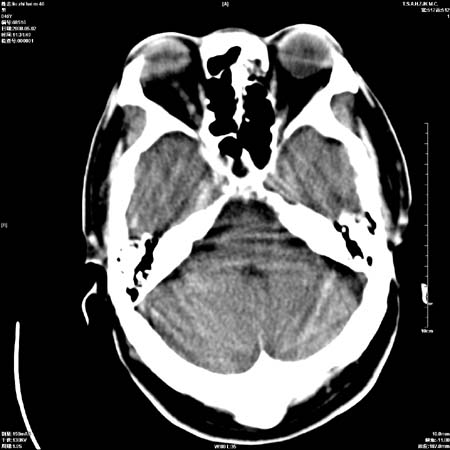

男性   46岁   头晕头痛一周    无任何外伤史    有高血压病史

亚急性硬膜下血肿

考虑双侧慢性硬膜下出血

支持双侧慢性硬膜下血肿。

应该是亚急性(3天——3周)硬膜下出血

亚急性硬膜下血肿;典型。